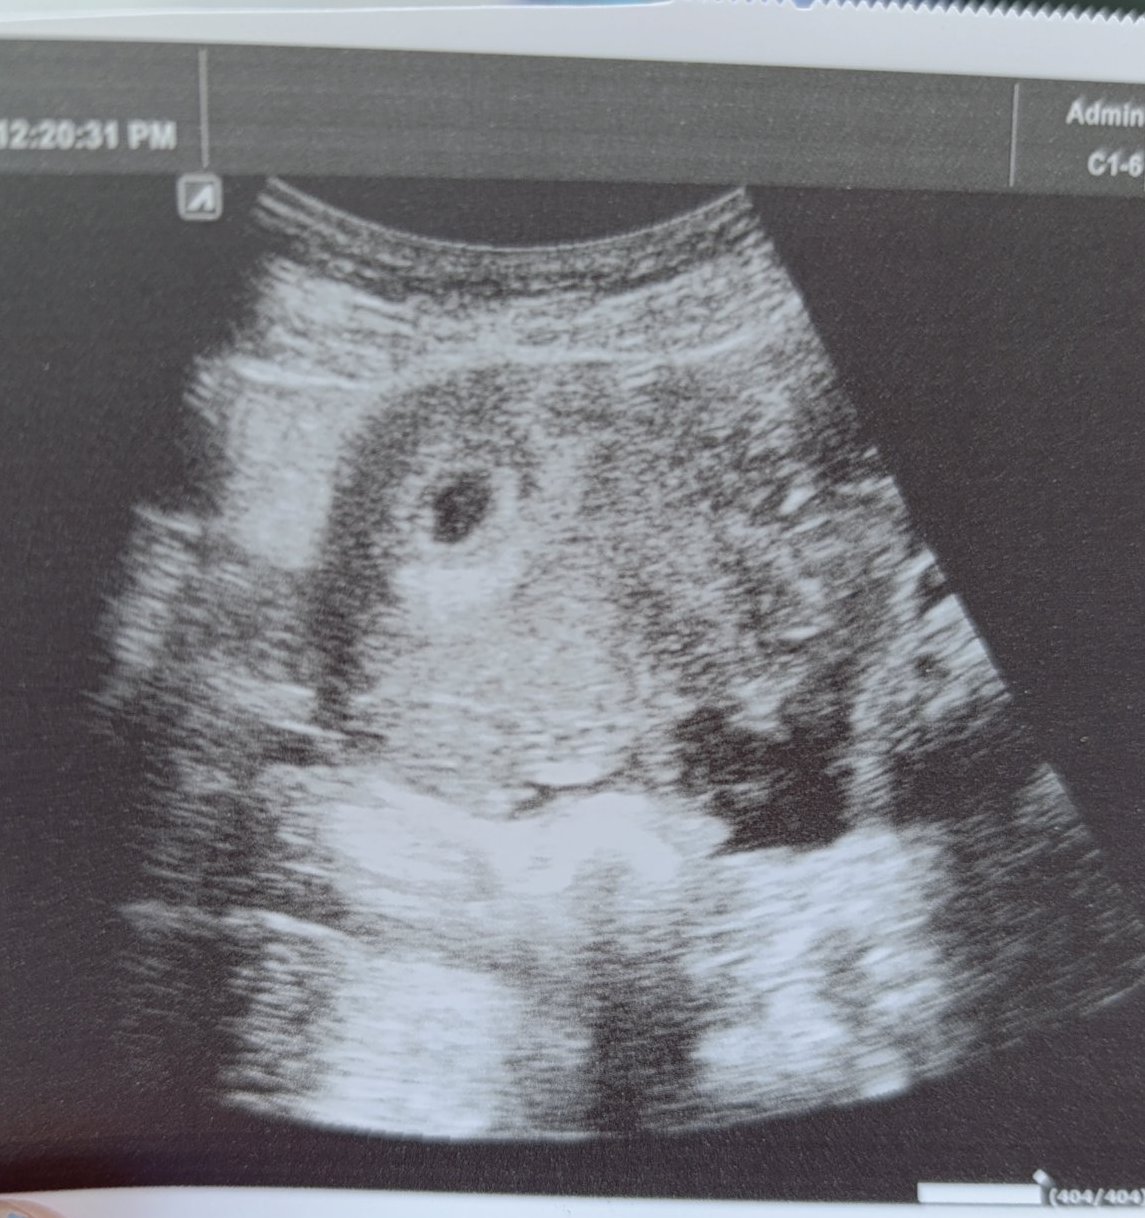

Здравейте момичета. Преди седмица разбрах ,че съм бременна с 2 положителни теста. Бях на гинеколог ,който ми каза ,че са две. Бяхме го хванали 30мин преди края на работното му време и нищо друго не ми каза освен ,че са 2 нито коя седмица съм нито термин обсолютно нищо! Казах му че последните 2 3 седмици кашлям много ,но той ми каца буквално цитирам ,,НЯМА СТРАШНО'' Не ми предписа нито витамини нито нещо за кашлицата... Мина се една седмица кашлянето продължаваше и при всяко изкашляне ме прерязваше ниско долу много гадно чувство. После си казах ,че аз обезателно трябва да отида при друг гинеколог да ме прегледа и да ми даде нещо за кашлицата... Днес отидох страхотен професионалист и да бременна съм ,но той каза ,че е само едно. Попита ме за снимка от първия ултразвук и му показах тази и той каза ,че е било възможно да са били 2 ,но от кашлицата и напъните да се е случило нещо. Обясни ми за синдрома за изчезналия близнак ,но също така му направи впечатление неговият колега колко безхаберно си е свършил работата като дори за кашлицата не ми е дал нищо! Отчаях се много... Тази снимка е от първия ултразвук като коментар ще прикача новата снимка. Та въпросът ми е на тази първата според вас наистина ли са 2 или нещо се е объркал първият доктор?

Изглеждат две на тази снимка. Не съм медицинско лице, но съм имала двуолодна бременност и ми прилича донякъде на това, което се видя на първи преглед при мен.

Две сакчета са според мен.

На първата снимка си пише, че са два обекта.